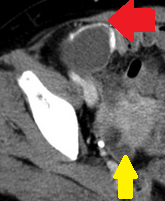

Σχήμα 1 . Η αξονική τομογραφία με ενισχυμένη με σκιαγραφικό έδειξε μια ακανόνιστη περιφερική μάζα στο αριστερό μισό του εγκάρσιου κόλου με λιπώδη συσσωμάτωση δίπλα σε παχυσμένο τοίχωμα του εντέρου. ( Ευγενική παραχώρηση Δρ. Β. Πενόπουλος ) .